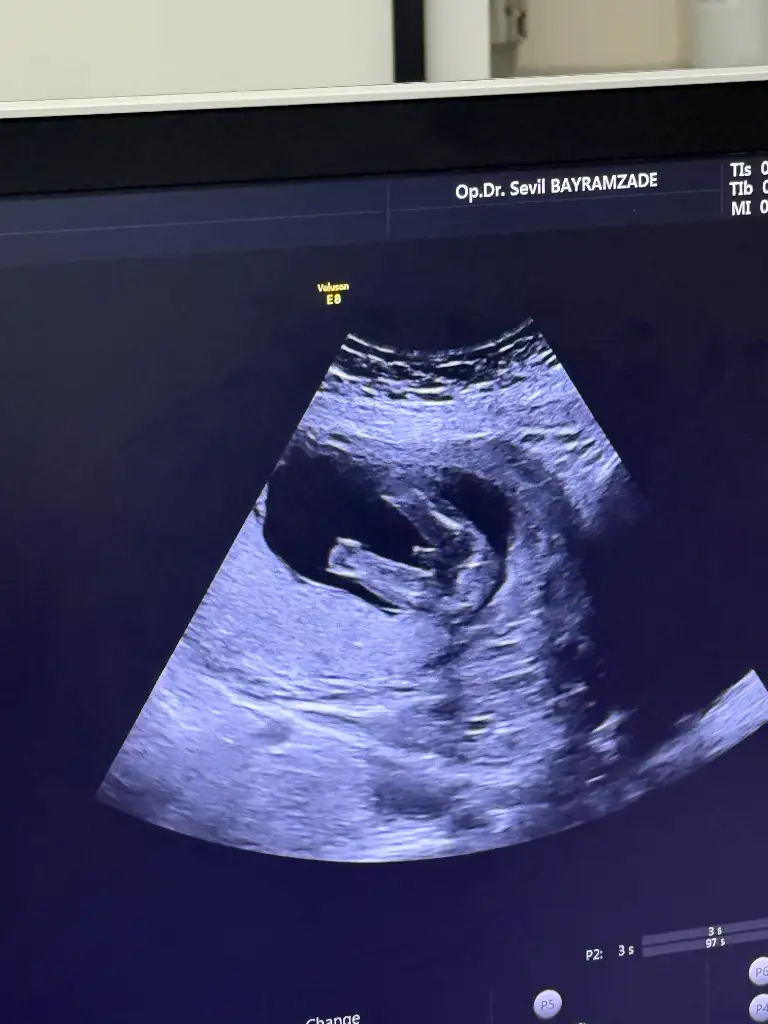

Merhaba hanımlar 17+2 haftalık hamileyim. 15 haftada erkeğe benziyor dedi 16+4 te erkeğe benziyor baya uğraştı belli erkek dedi bacak arasını gösterdi bende gördüm. Bugün tekrar gittim başka doktora bana kız gibi dedi kesin mi dedim %70 dedi kesin diyemem dedi. Bana erkek dediler hatta gösterdi diyor ben görmedim 3 çizgi gördüm kız gibi dedi. Kafamı allak bullak ettiler. Bu da ultrason görüntüsü

Bulantı ve kusurlarınızı flan varmiMerhaba hanımlar 17+2 haftalık hamileyim. 15 haftada erkeğe benziyor dedi 16+4 te erkeğe benziyor baya uğraştı belli erkek dedi bacak arasını gösterdi bende gördüm. Bugün tekrar gittim başka doktora bana kız gibi dedi kesin mi dedim %70 dedi kesin diyemem dedi. Bana erkek dediler hatta gösterdi diyor ben görmedim 3 çizgi gördüm kız gibi dedi. Kafamı allak bullak ettiler. Bu da ultrason görüntüsü